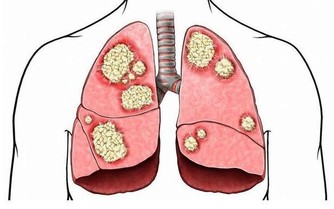

3.心血管內科醫生:不要在疲勞時喝咖啡或濃茶

不要以為疲勞時喝咖啡或濃茶可以提神,其實那容易對心血管系統造成傷害,

許多人也會以吸菸來紓壓,那也會對身體的傷害加倍。